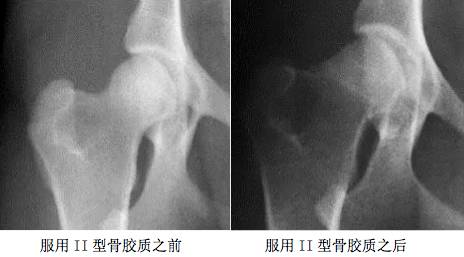

2006年3月9日,美国专利Kolla2 研究团队经过临床试验证明服用【骨精华】主要成份II型骨胶质(kolla2)六周后,患有关节发育异常的犬科动物恢复了正常运动功能,随后的X光射线显示髋关节软骨明显增厚,恢复正常。以下为服用II型骨胶质Kolla2前、后X光对比图: